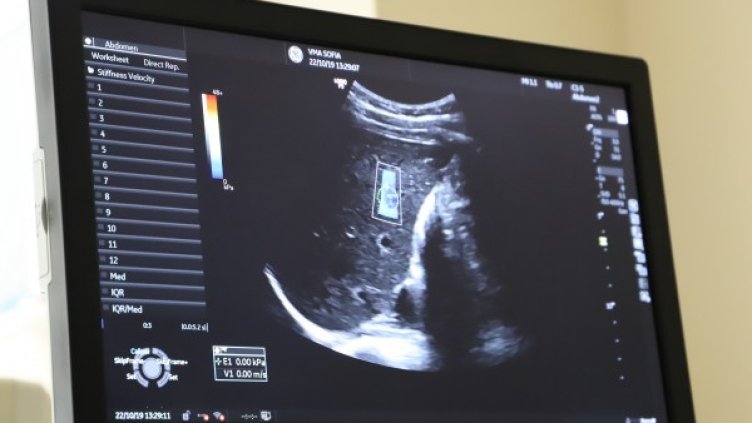

Безплатно тестване за хепатит С, което се извършва от 18 май в УМБАЛ „Св. Иван Рилски“, ще бъде удължено с една седмица, съобщиха от болницата.

Пациентите ще имат възможност да се изследват до 29 май. Запазва се изискването за предварително записване на тел. 0876 01 39 13, а пробите ще се вземат от 11:00 до 14:00 часа. Причината за удължаване на срока е в големия интерес към инициативата.

Затова от болницата са решили да удължат кампанията с още една седмица. Както и в първоначалния етап, методът за тестване, който ще се използва, няма да е от типа на т. нар. бързи тестове, а серологичен, който е с най-висока чувствителност и специфичност

„Това, което установихме до тук, е, че средно на 4 изследвали се, един е с положителна проба за хепатит С. Това означава, че добре сме се ориентирали в кои групи да търсим заразените“, коментира проф. Красимир Антонов. Преди седмица той алармира, че България драстично изостава в намирането на носителите на коварната болест. Смята се, че у нас нейната честота е 1,1%, което прави около 77 000 души. Поради липсата на симптоматика и на профилактика над 90 % (около 69 000 души) не знаят, че са заразени и съответно не се лекуват.

Пациенти, при които се установи инфекция, ще бъдат пренасочвани за безплатна консултация и назначаване на терапия в Клиниката по гастроентерология на УМБАЛ „Св. Иван Рилски“, където се намира най-големият център за лечение на вирусни хепатити в България.